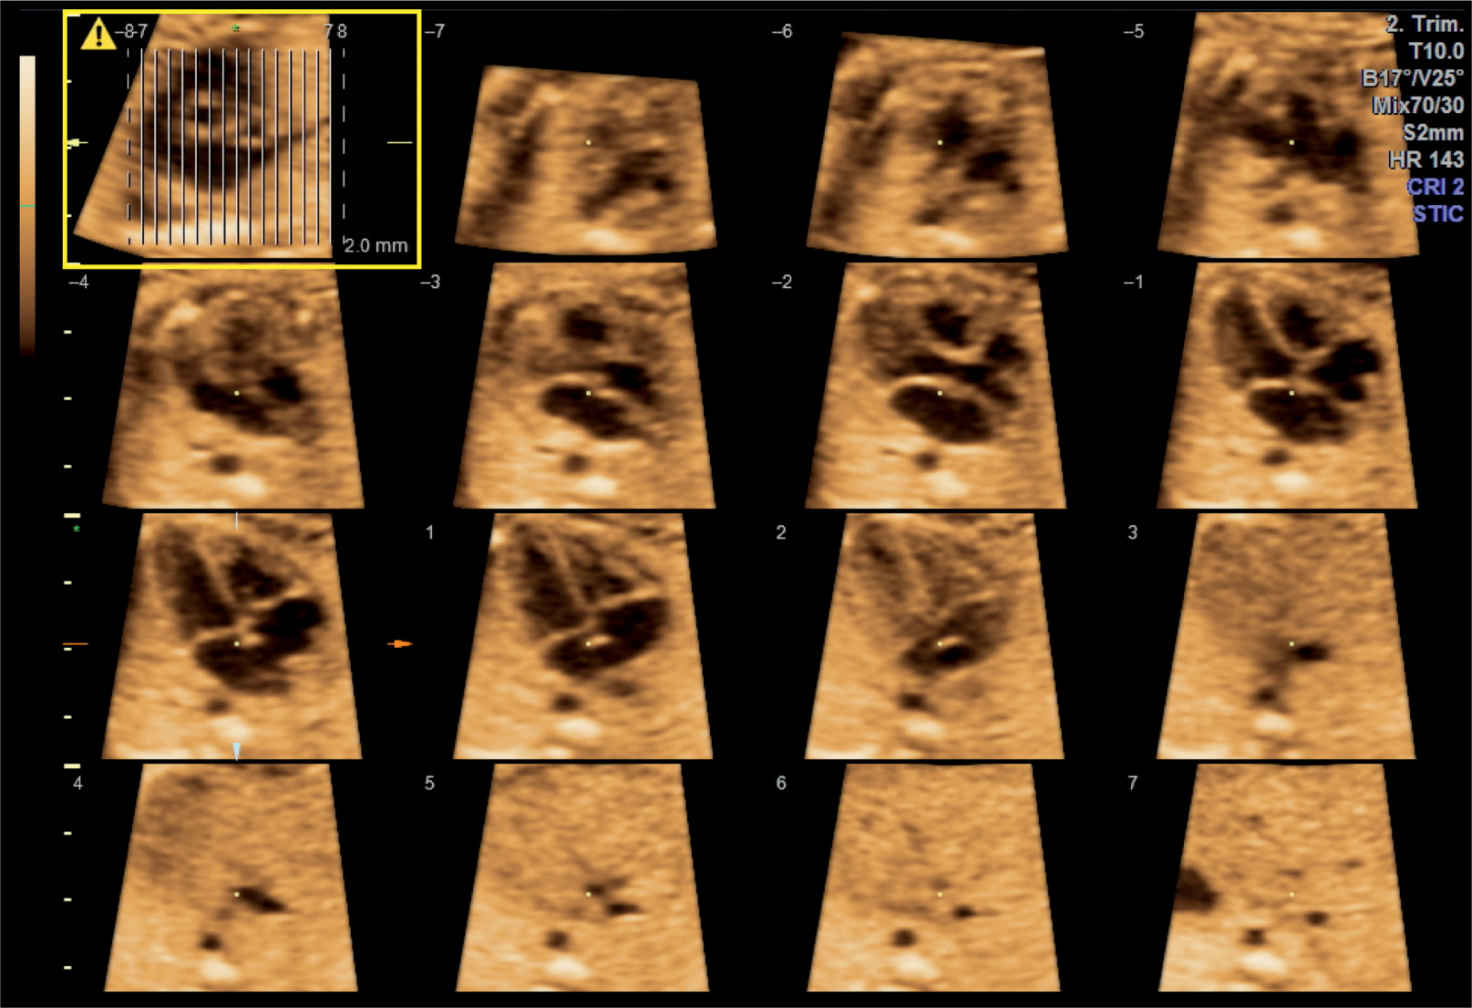

3d Ultrasound Of The Heart What Does A Shadow On The Heart Mean In An Ultrasound The cardiac contour is abnormal with bulging on the right giving a double right heart border (1), prominence of the left atrial appendage (2). An echocardiogram is a test that uses ultrasound to show how your heart muscle and valves are working. The heart shadow is a critical review area on the chest radiograph. Acoustic shadowing occurs when an ultrasound. What Does A Shadow On The Heart Mean In An Ultrasound.

3d Ultrasound Of The Heart What Does A Shadow On The Heart Mean In An Ultrasound Ultrasound, or sounds higher than we. An echogenic intracardiac focus (eicf) is a small white spot that may be seen on your baby's heart during one of your routine ultrasounds. An echocardiogram is a test that uses ultrasound to show how your heart muscle and valves are working. Heart problems are the most common congenital birth defects, and it’s easy. What Does A Shadow On The Heart Mean In An Ultrasound.

3d Ultrasound Of The Heart What Does A Shadow On The Heart Mean In An Ultrasound The cardiac contour is abnormal with bulging on the right giving a double right heart border (1), prominence of the left atrial appendage (2). Heart problems are the most common congenital birth defects, and it’s easy to panic when something unusual is detected on ultrasound. Ultrasound, or sounds higher than we. An echocardiogram is a test that uses ultrasound to. What Does A Shadow On The Heart Mean In An Ultrasound.